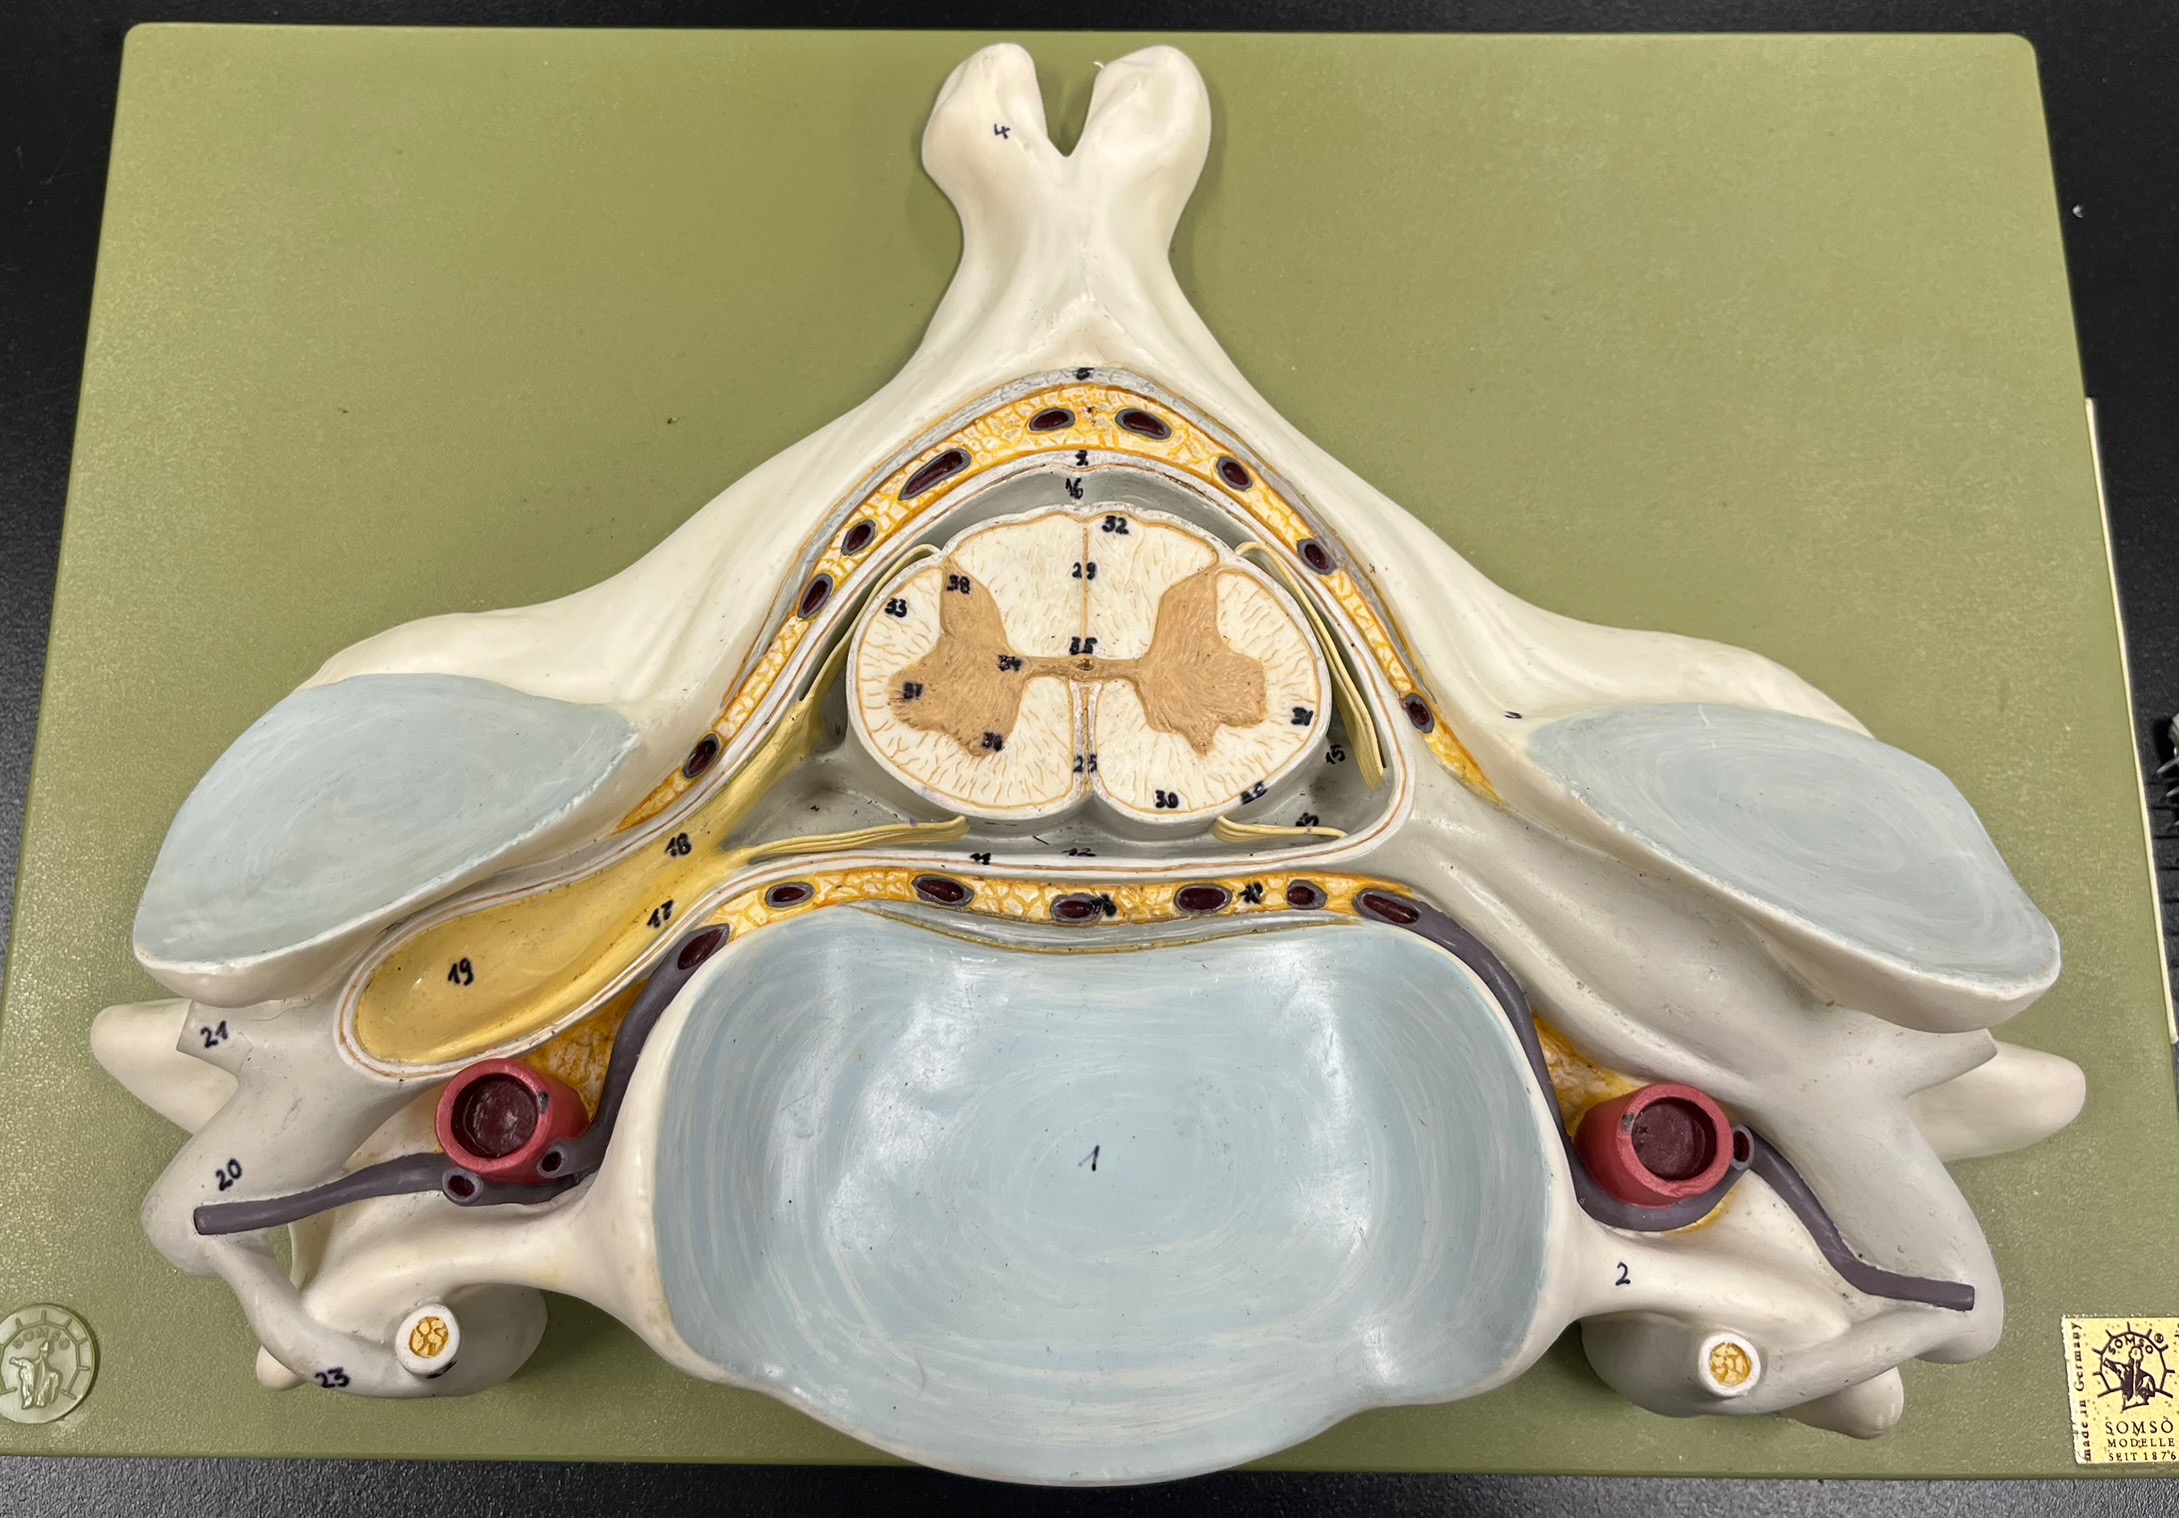

epidural space

dura mater

subdural space

arachnoid mater

subarachnoid space

pia mater

denticulate ligaments

What is the groove here?

anterior median fissure

posterior median sulcus

posterior (dorsal) horn

posterior (dorsal) horn; R—>L

anterior (ventral) horn

lateral horn (selected models)

gray commissure

central canal

anterior column

lateral column

posterior column

white commissure

posterior (dorsal) root ganglion

What is the bulb here?

posterior (dorsal) root ganglion

posterior (dorsal) root

posterior (dorsal) root

anterior (ventral) root

anterior (ventral) root

dorsal ramus

dorsal ramus

ventral ramus

ventral ramus

rami communicantes

rami communicantes

sympathetic chain ganglia

sympathetic chain ganglia